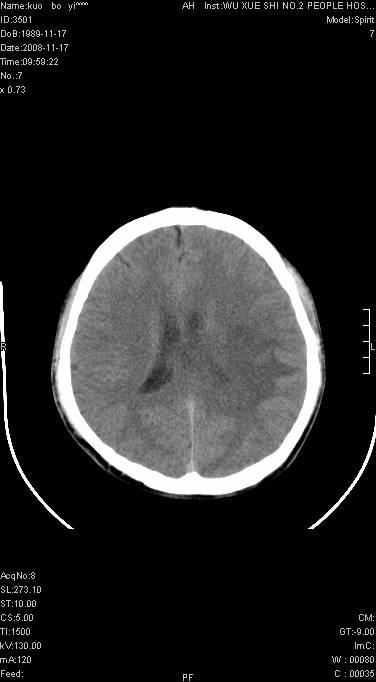

增强后水肿中心高密度灶有明显强化,强化不均匀,呈雪花状或絮状,且强化明显,若为肿瘤,应该出现形态较规则的瘤体影,强也有例外如胶质瘤就可以形态不规则.但胶质瘤明显强化者多为恶性间变性,与病史及相关表现太不相符.因此本例多考虑为炎症引起.

患者年龄才19岁,病史很短,也较符合炎症等短程病变.

考虑左侧顶叶脑炎可能;建议追踪复查。

左顶叶较大范围水肿区,内见明显强化的片状 棉絮状组织,但占位效应不明显。多考虑:脑炎!

左顶叶大范围水肿,内见明显强化的片状 棉絮状组织,但占位效应不明显。考虑脑炎可能性大。